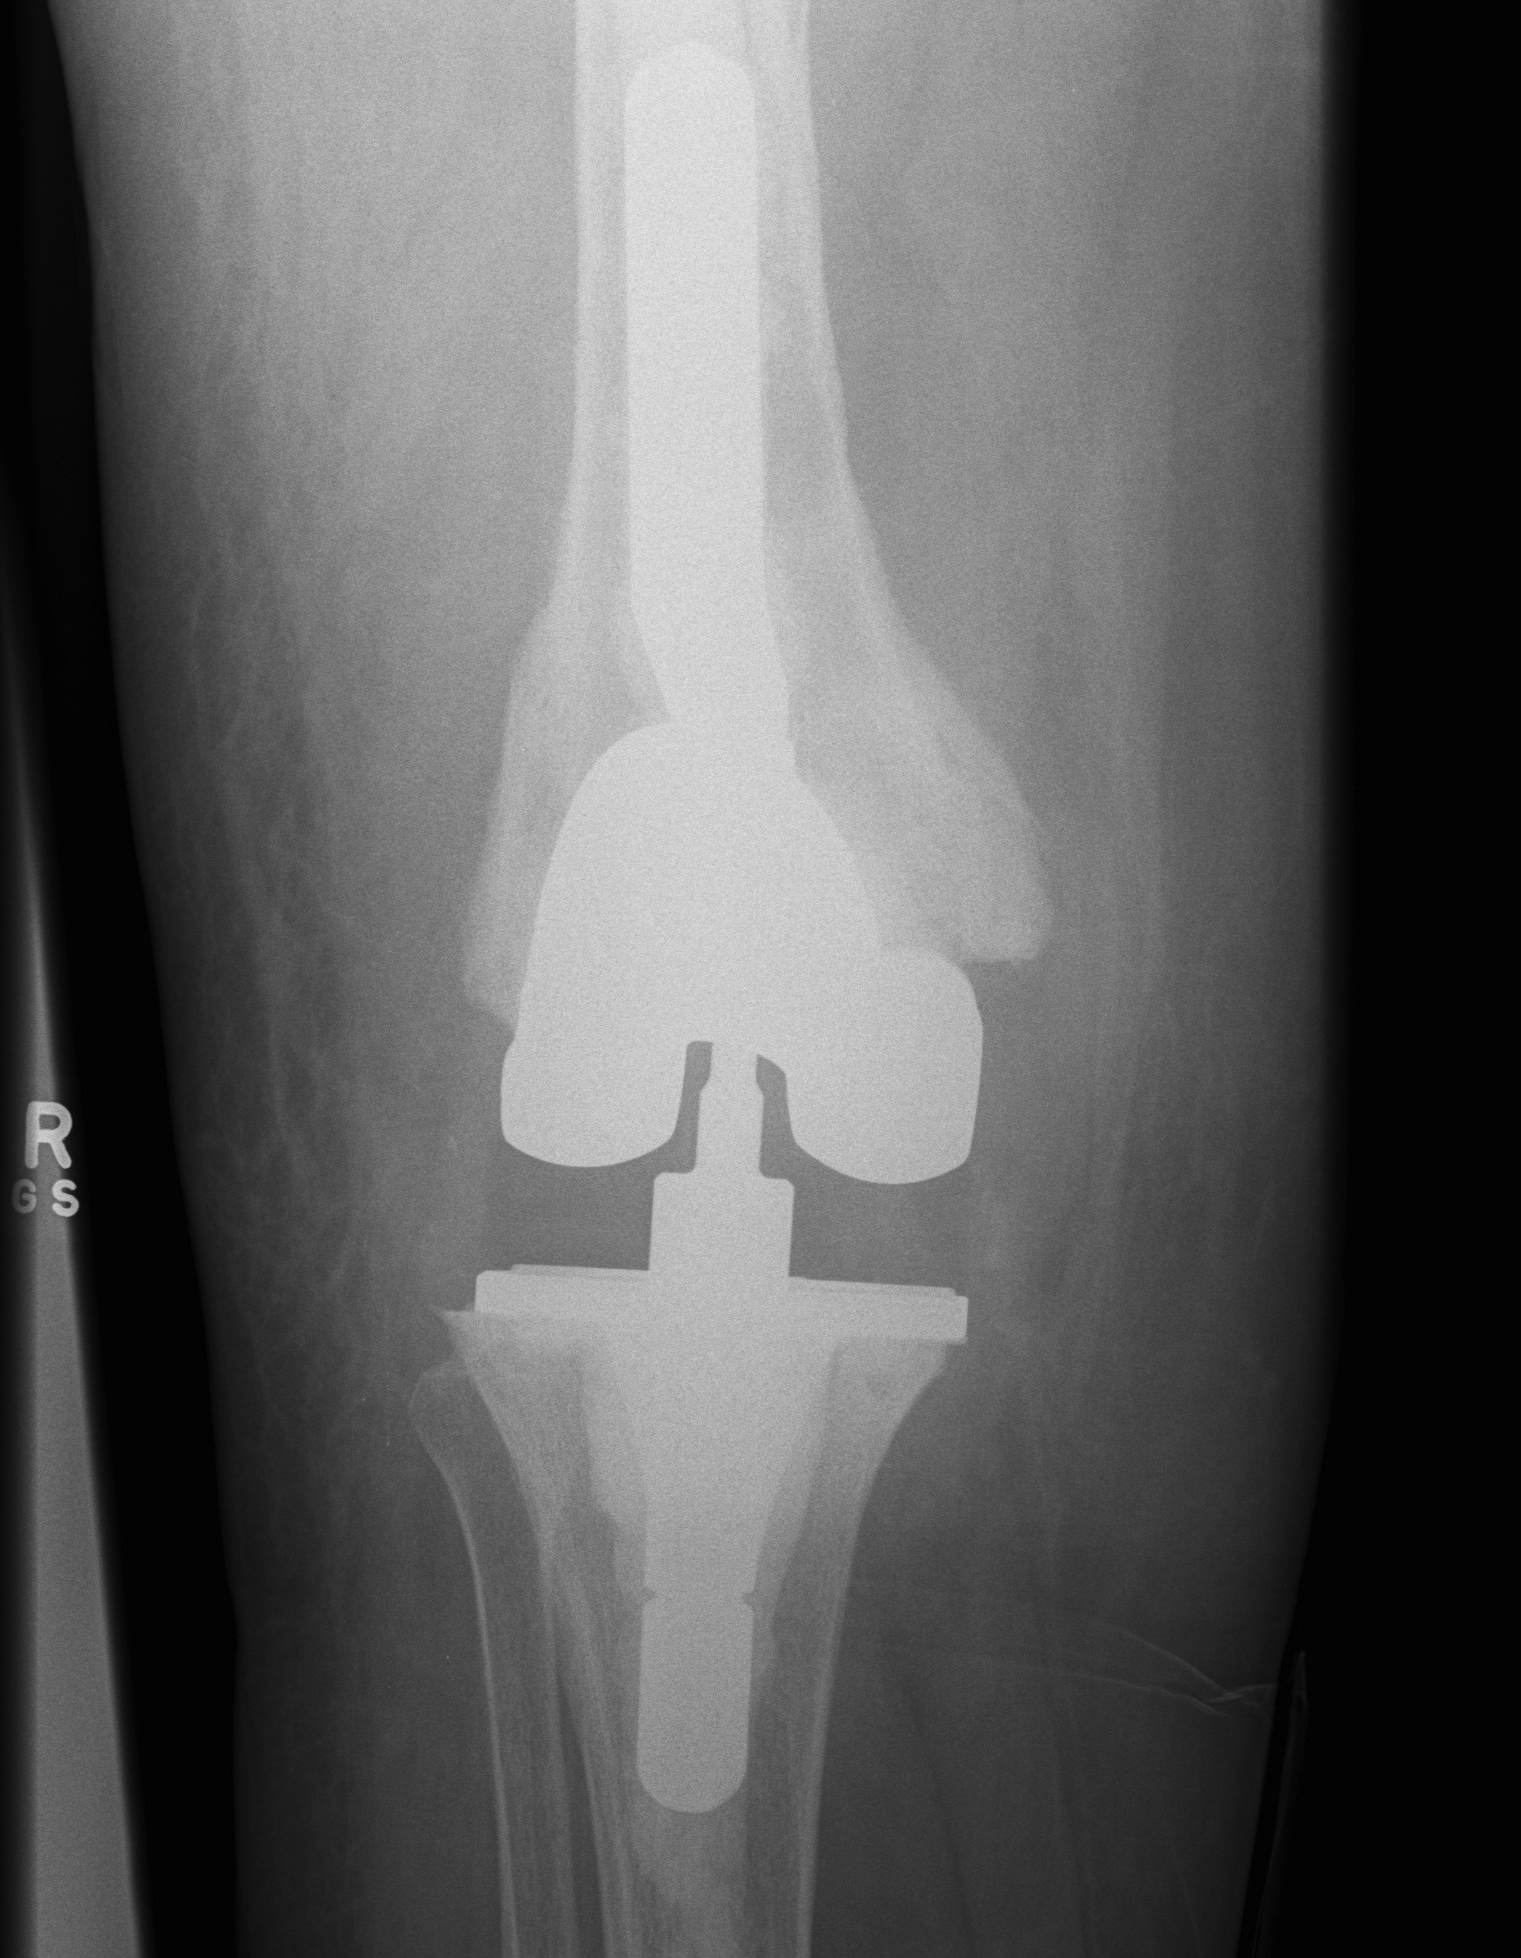

2. Constrained Non Hinged / Varus Valgus Constrained (VVC)

Design

1. Large metal reinforced post in deep femoral box

- provides greater coronal plane stability

- variable varus/valgus stability as well as rotation

- permit 2-3o of varus-valgus movement

- 2o of internal/external rotation

2. Stems

- transmit the increased stresses away from the fixation interfaces to diaphysis

- otherwise increase risk of early loosening